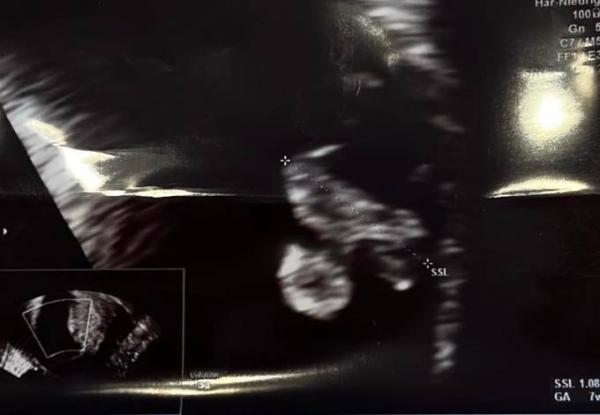

Hallo zusammen kennt sich jemand mit der Remzi Methode aus... Kann mir jemand sagen welches Geschlecht es laut Ramzi Methode hat

Bild zu Ramzi Methode - Schwanger - wer noch? Rund um die Schwangerschaft

Laut Theorie ein Junge. Meine 2. Jungs lagen beide auf der rechten Seite (laut Theorie ein Mädchen). Du hast eine 50/50 Chance ^^ da bleibt nur abwarten

Ehrlich jetzt? Jetzt antworte ich dir, LeFyNi, zum 3. Mal, dass das US-Bild gedanklich umgedreht werden muss, da der Muttermund unten dargestellt ist und bei der Rampi-Methode aber oben ist. Da der Embryo dann auf der rechten Seite liegt ist es laut Theorie dann ein Mädchen.

Hey, Ich habe heute auch ein Bild bekommen,  laut meinem Arzt bin ich in der 6ssw. Könntet ihr mir sagen was ihr denken würdet mit der ramzi methode? Mein Arzt möchte mir einfach nix sagen wo ein Ansatz wäre usw weil sie das ja nicht dürfen bzgl geschlecht. Das Bild ist vaginal geschallt Liebe grüße